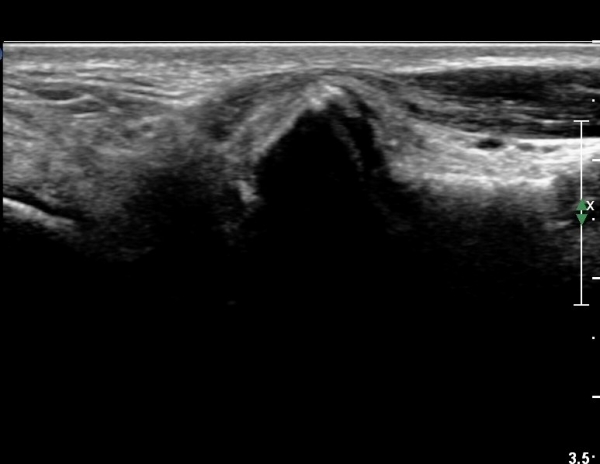

Á¾°ñ Àü¹æ µ¹±â(anterior process) °ñ±Ø°ú Ȱ¾×¸·¿° ¼Ò°ßÀ» º¸ÀÓ(»çÁø 3, 4).

Sinus tarsi Á¾´Ü¸é, Ⱦ´Ü¸é°Ë»ç¿¡¼­ sinus tarsi ³» ºÎÁ¾À» º¸ÀÓ(»çÁø 5, 6).